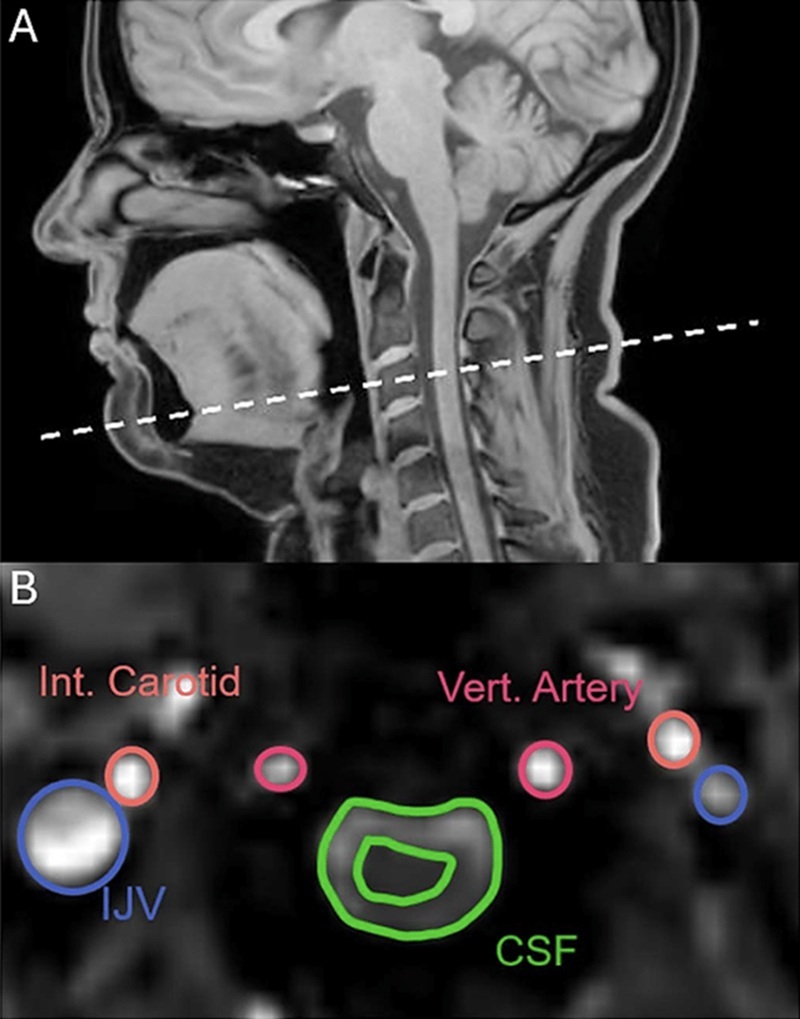

Istraživački tim koristio je magnetsku rezonanciju (MRI) kako bi skenirao glave i vratove 22 zdrava sudionika. Sudionici su dobili upute da zijevaju, duboko dišu, pokušaju suzbiti zijevanje te da dišu normalno.

Budući da zijevanje i duboko disanje dijele slične mehanizme, znanstvenici su očekivali da će snimke pokazati slične obrasce. Međutim, rezultati su ih iznenadili. Za razliku od dubokog disanja, koje nije mijenjalo smjer protoka cerebrospinalne tekućine, zijevanje je tu tekućinu usmjeravalo dalje od mozga.

Neuroznanstvenik Adam Martinac izjavio je za časopis New Scientist: „Zijevanje je pokretalo kretanje cerebrospinalne tekućine u suprotnom smjeru nego tijekom dubokog udaha.“

Analiza je pokazala i da i duboko disanje i zijevanje povećavaju protok krvi koja napušta mozak, čime se stvara prostor za dolazak svježe krvi. Zanimljivo je da se smjer protoka krvi nije mijenjao tijekom zijevanja.

Međutim, u početnoj fazi zijevanja dolazi do naglog povećanja protoka krvi kroz karotidne arterije prema mozgu, i to za otprilike jednu trećinu. Ovaj podatak mogao bi upućivati na to da zijevanje ima više funkcija nego što se dosad pretpostavljalo.